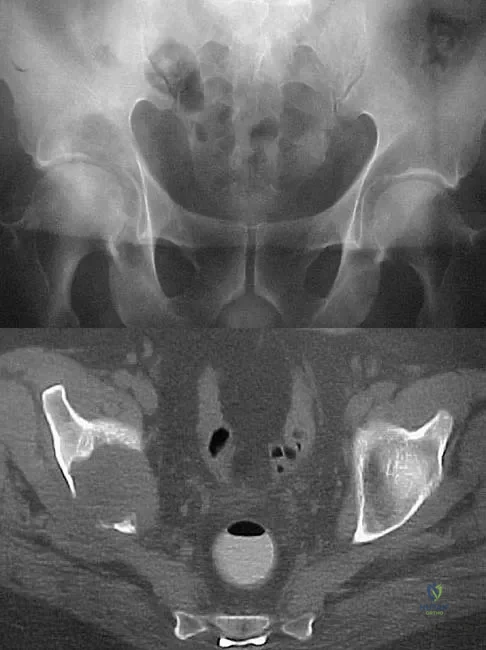

A 50-year-old man with metastatic renal cell carcinoma has right hip pain. A radiograph and CT scan are shown in Figures 48a and 48b. The first step in management should consist of

Explanation